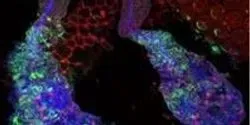

The scientists say the method, which they based on tests with mouse embryos and thousands of human cells, could improve consistency and efficiency of genome editing